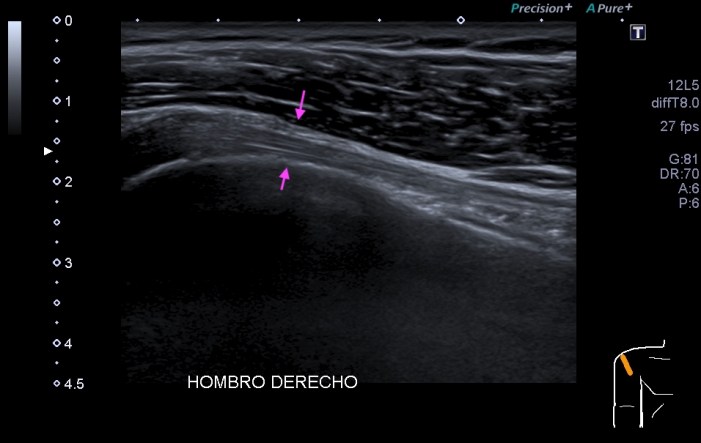

317. El tendón. Tipos y patología.

En Eco Msk uno de los objetivos principales de estudio es el tendón y su patología, lo primero es entender bien el tipo de tendón que vamos a estudiar, para posteriormente comprender bien que le está pasando y por la razón que puede estar sufriendo y es que no es igual un tendón de anclaje o de deslizamiento. Me explico:

Tendinopatías y desgarros parciales:

• Perdida focal o difusa de la ecoestructura tendinosa.

• Engrosamiento del tendón aun manteniendo su eoestructura (comparar siempre el lado contralateral)

• Angiogénesis en pacientes sintomáticos.

• Heterogeneidad como alto indicador de desgarros focales y marcador de mal pronóstico.